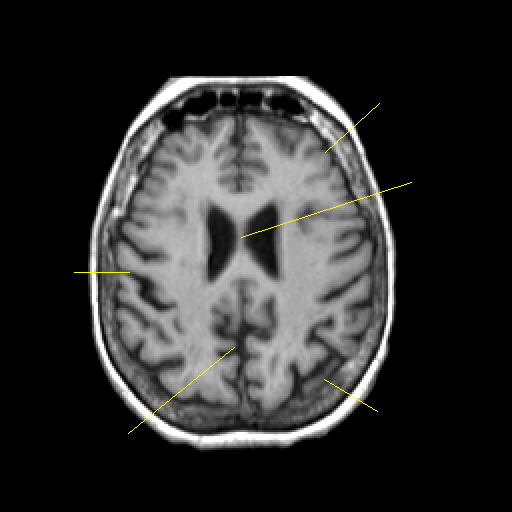

T1-weighted structural MR: Slice 35

Slice 35

Unlabeled

Pointers

Labeled